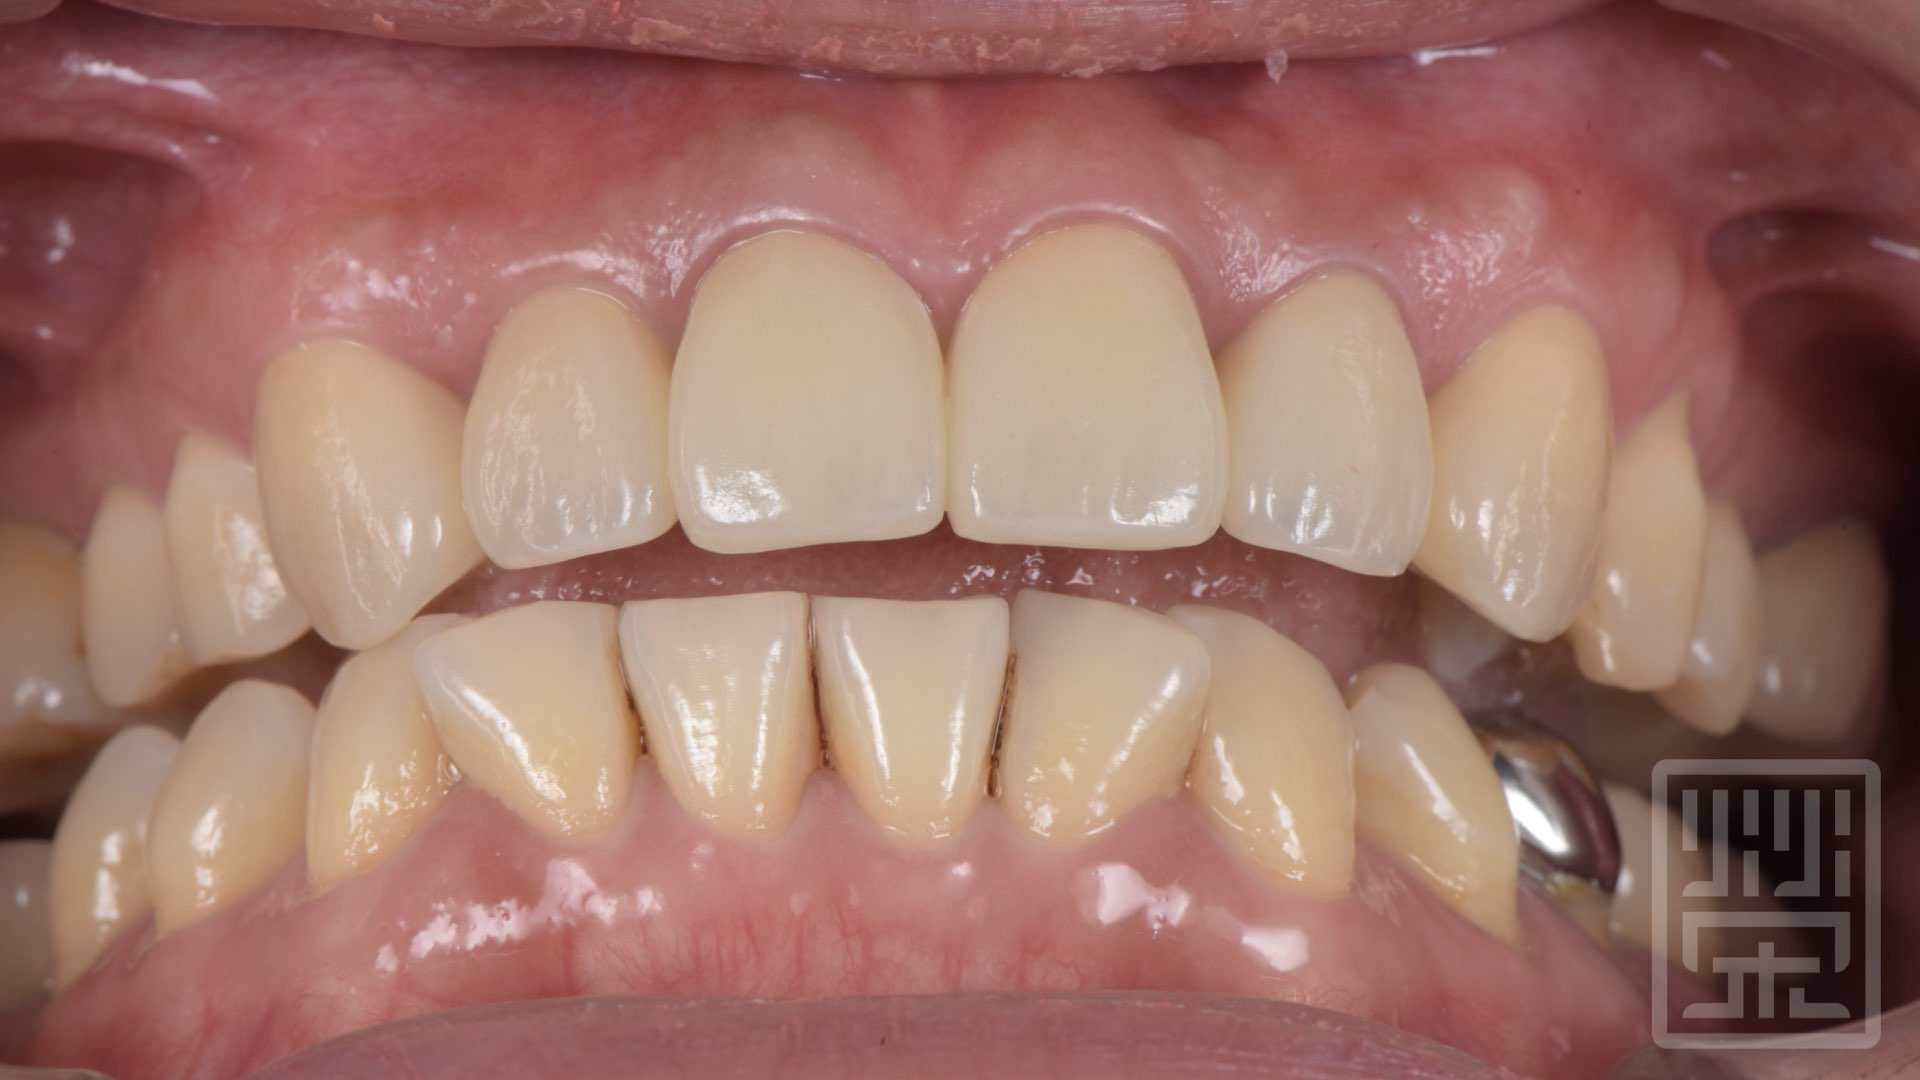

植牙全瓷冠修復

保護性咬合